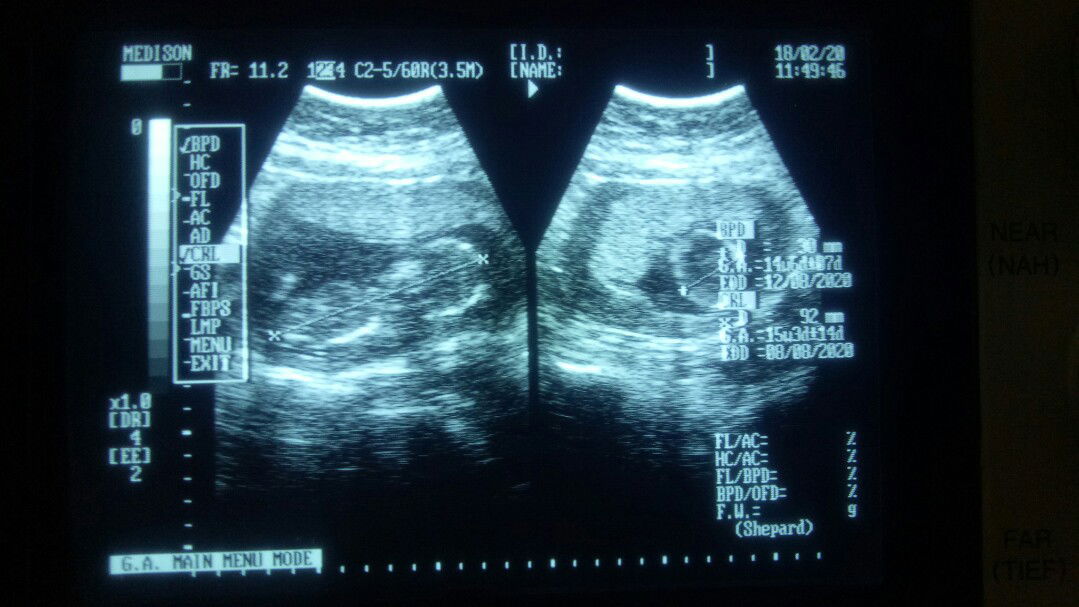

Bunda2 aku mau tanya dong aku kan hamil usia 7 Minggu pas di usia 5minggu USG sudah ada kantung janinnya Pas 7minggu aku flek selama 3hari di hari ke 3 aku USG lagi kata dokternya kantungnya sudah ga ada besoknya aku USG transvaginal juga sama sudah ga ada kantungnya Kata dokternya tunggu sebulan lagi baru diperiksa lagi gimana ya Bun apa aku coba kedokter lain yaa ada yg punya pengalaman kah serupa kaya aku tolong di bantu jawab dan sarannya yaa#SeriusTanya #Sharing_dong_Bund